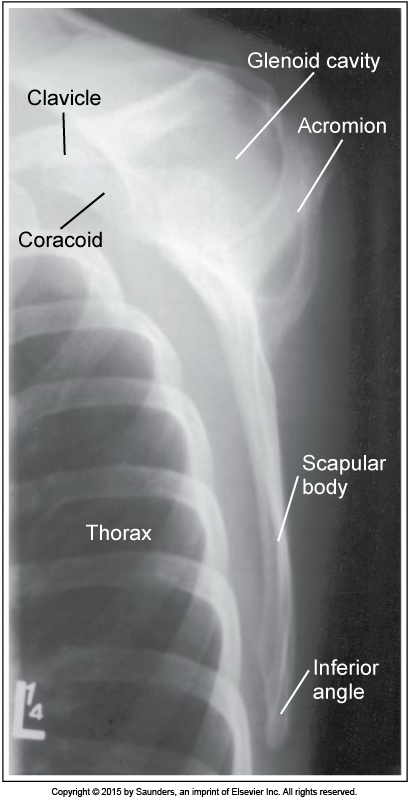

lateral scapula

accurate positioning